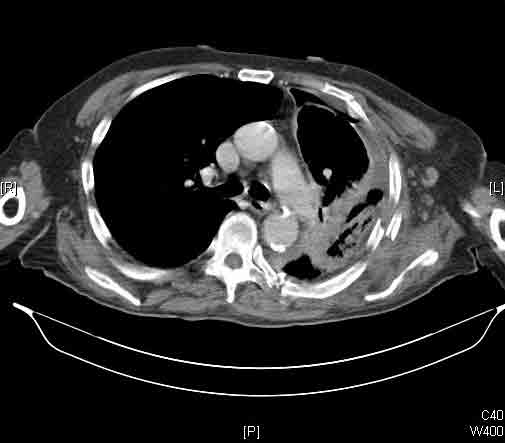

Here we present, as a paradigm of repair, the case of a 65 year old gentleman referred to our institution for an indolent mass in the left anterior chest wall. Repairs for other conditions follow the same rules. This mass had been stable in size for more than 12 months and the patient was prompted to seek medical attention as, after weight loss due to dieting, he felt the mass was uncomfortable while sleeping. Apart from coronary stenting for angina, the past medical history was unremarkable.

Computed tomography scan of the chest showed a mass protruding from the cortex of the third rib. A percutaneous core biopsy was non-diagnostic. We proceeded to an open incisional biopsy. This was reported as showing a spindle cell neoplasm. The patient was therefore scheduled, after multidisciplinary meeting discussion, for radical surgery.

At surgery, the mass was arising from the cortex of the third rib, and solid measuring 5x8 cm. There was no macroscopic involvement of the surrounding extra-thoracic musculature or of the underlying lung, the mass being confined to the rib and intercostal muscles. The patient underwent resection of the second to fourth ribs and the rhomboid muscle as well, in the attempt to get clear margin. The large antero-lateral defect was eventually reconstructed using 2 mouldable titanium bars. To prevent lung herniation through the defect, we reconstructed the layers anatomically using a biological patch (Veritas®). The final histopathology was a low grade sarcoma of the chest wall with clear resection margins.